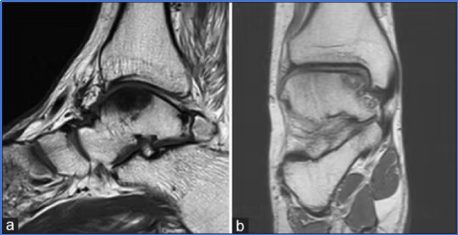

CLAI由于踝关节活动功能的异常,通常会产生滑膜增生、软组织撞击、骨性结构撞击、游离体、软骨损伤以及创伤性关节炎等。

未及时治疗的CLAI可能导致:关节内滑膜增生、骨赘撞击、游离体及软骨损伤,运动功能下降、生活质量降低,研究表明,早期恢复稳定性可有效减少软骨损伤的发生,尤其在运动员群体中更具临床意义。

图14: ab距骨软骨损伤